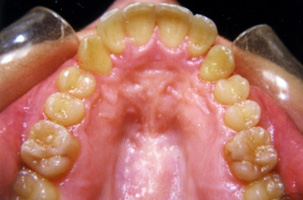

Υπερκάλυψη των κάτω προσθίων δοντιών, συνωστισμός, έγκλειστοι κυνόδοντες στην άνω γνάθο κι έκτοποι κυνόδοντες στην κάτω γνάθο. Ορθοδοντική θεραπεία σε συνδυασμό με γναθοχειρουργική αποκάλυψη των άνω κυνοδόντων.

Μετά τη Θεραπεία